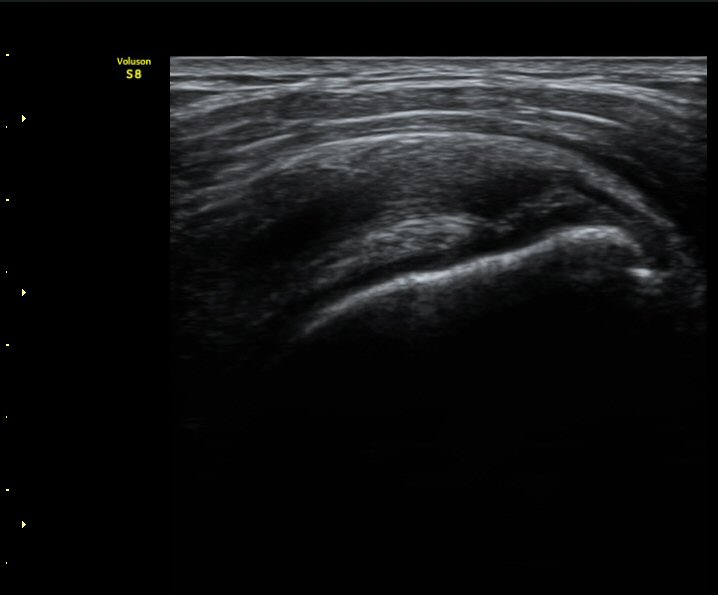

ÃÊÀ½ÆÄ °Ë»ç

2049205267_ba00cba1_IMG_20140331_2_3-c.jpg